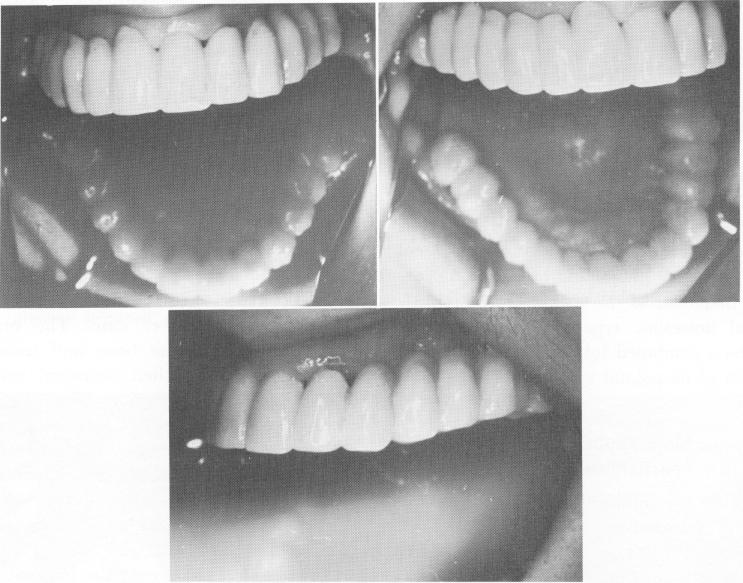

Fig. 11-185. The splint cemented in position.

1 Splint cemented on maxillary arch